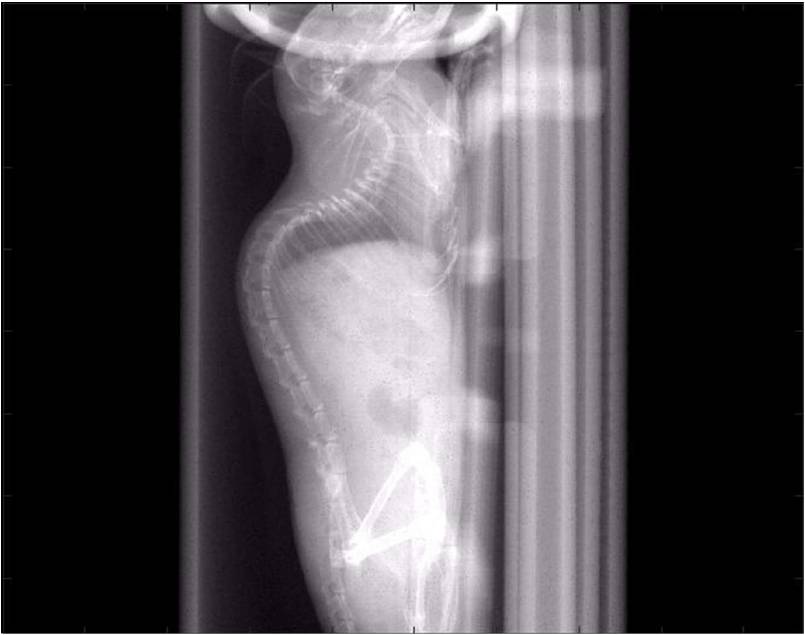

肺轉(zhuǎn)移

小鼠模式,22.5μm像素

正常

8天 14天

無造影劑注入 造影劑注入